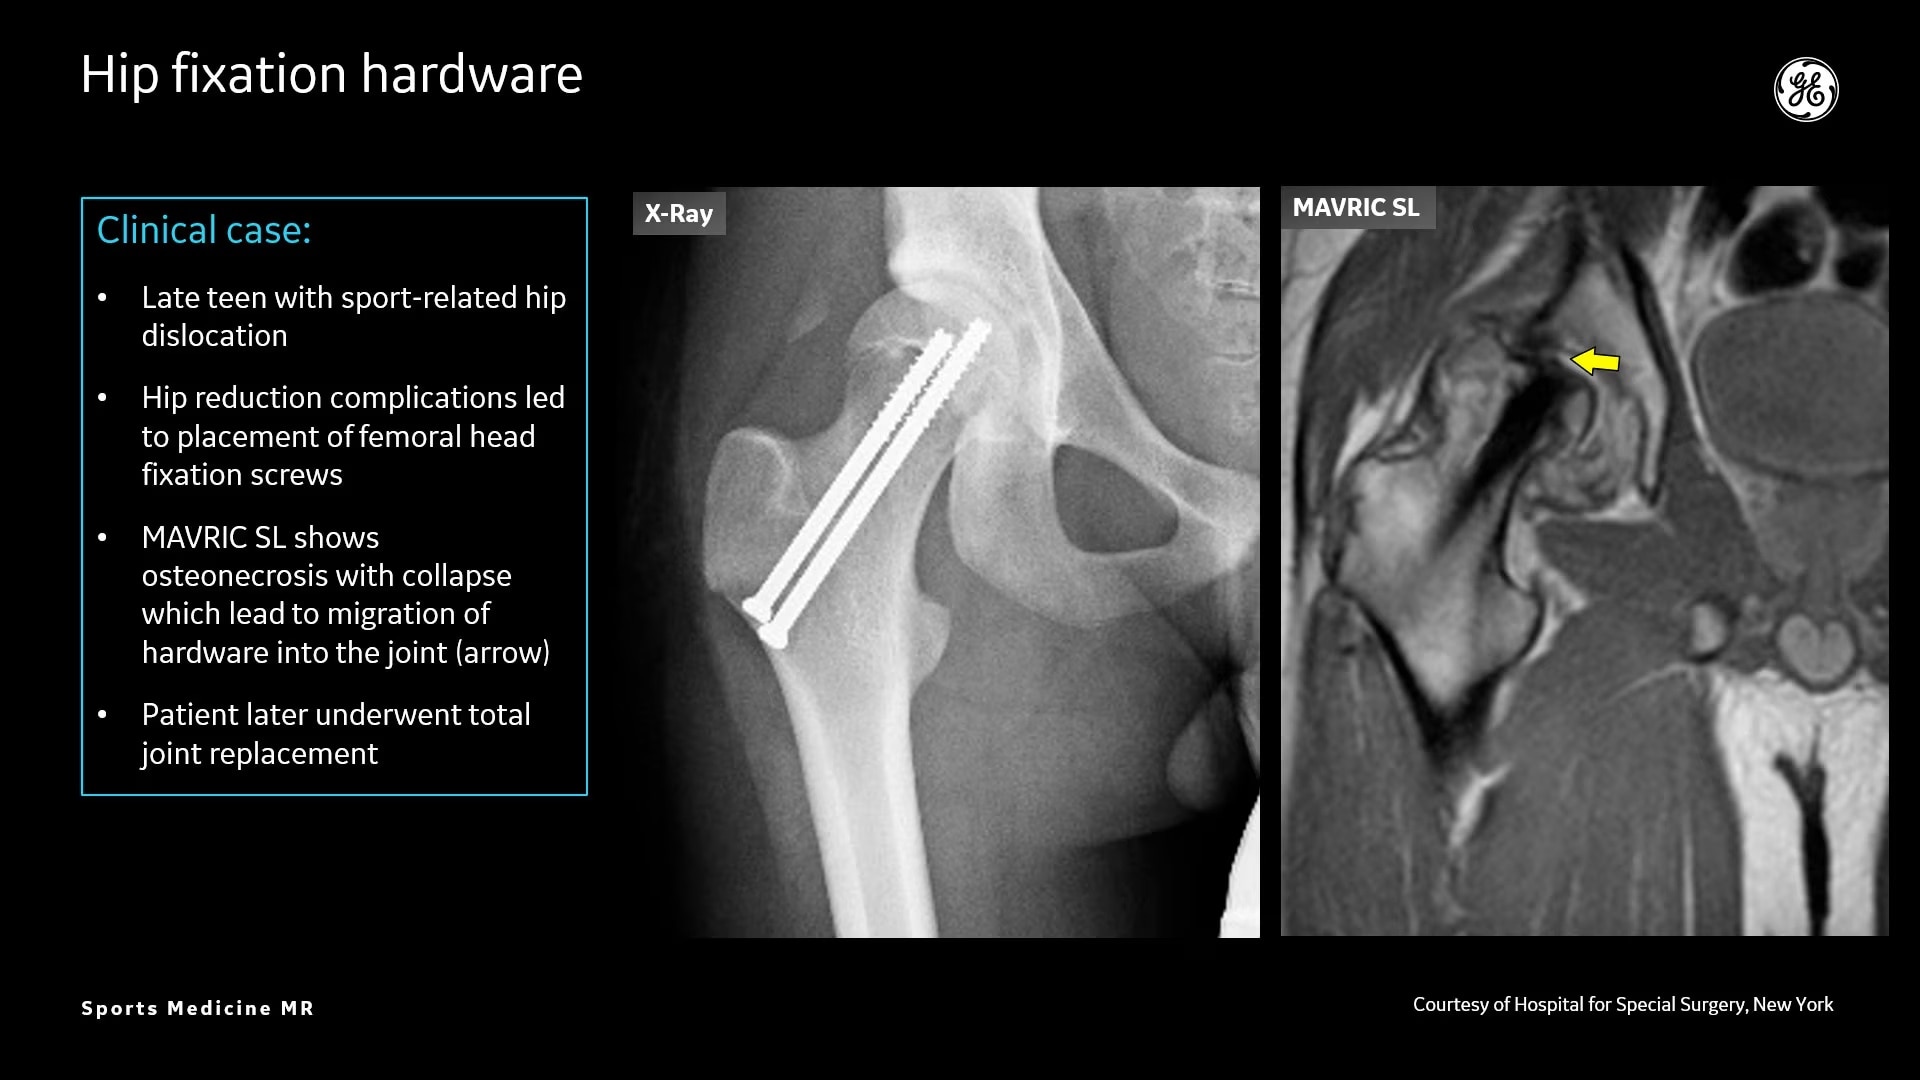

Osseous and Soft-Tissue Injuries

MR bone imaging technology to help diagnose an athlete’s injury

MR lacks ionizing radiation, and is well-suited for longitudinal evaluation of injury in adolescent athletes. The recent introduction of the three dimensional zero-TE (oZTEo) application provides exceptional bone contrast and, like CT, can be reformatted into any arbitrary plane.